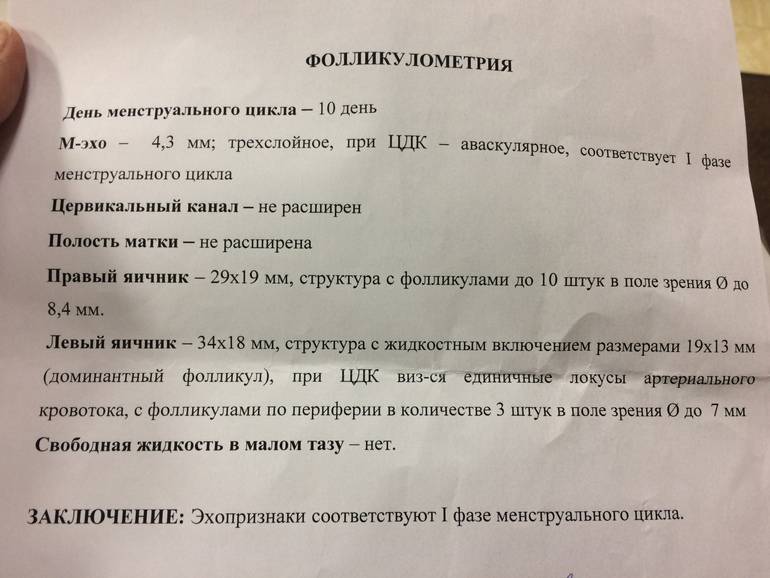

Созревание фолликула в яичнике: этапы и процессы